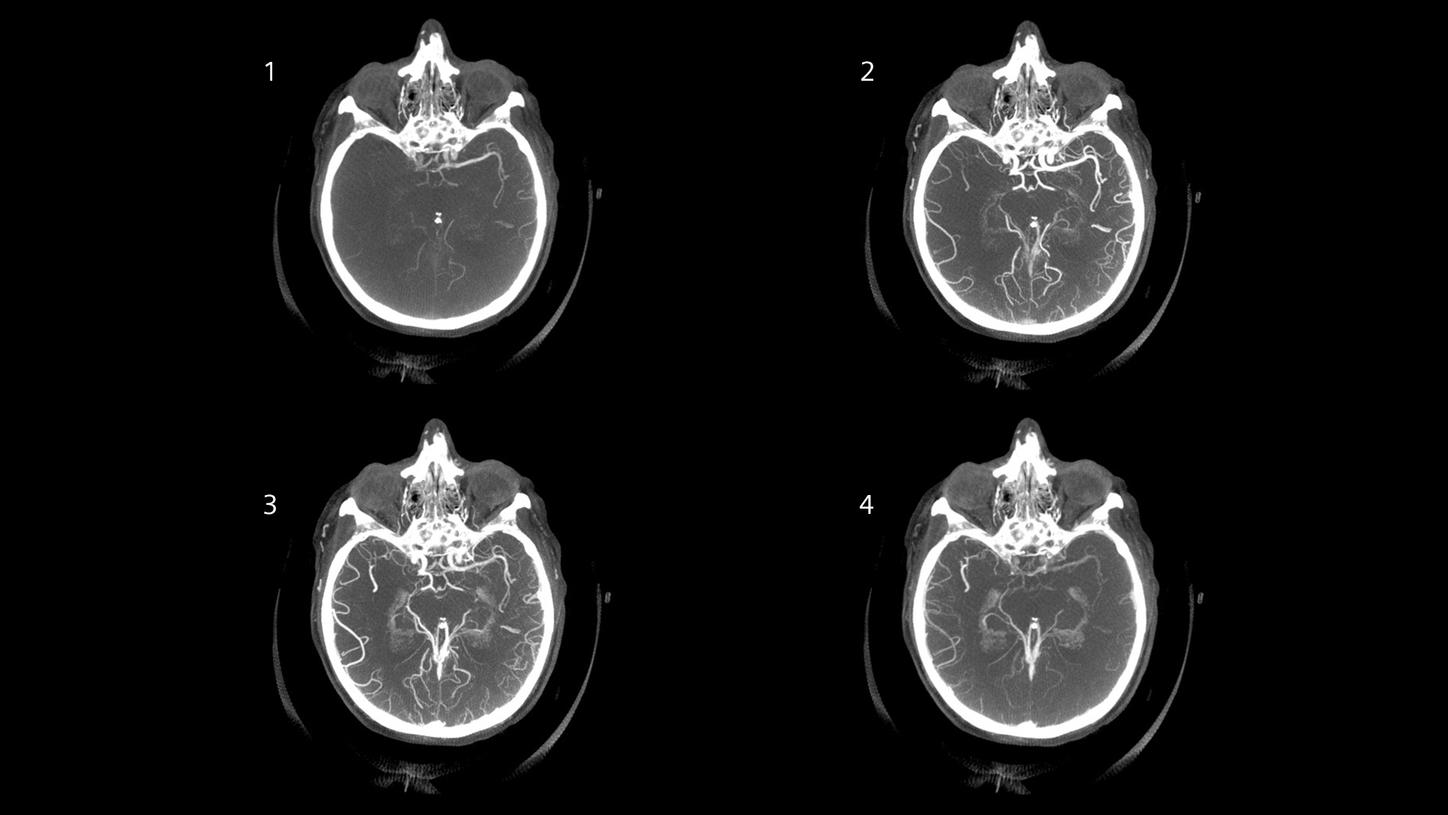

Angiography

CT planning of the following treatment with definition of occlusion length and collateral status and automated bone removal